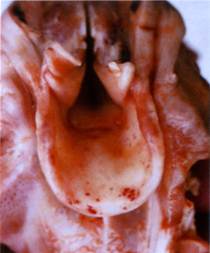

Селезенка свиньи при чуме

Макропрепарат. Селезенка свиньи при чуме (рис. 119)

Селезенка не увеличена, по ее краям видны множественные геморрагические инфаркты. Они округлой

Рис. 119. Селезенка свиньи при чуме.

ли треугольной формы, темно-красного цвета, несколько возвы-гаются над поверхностью селезенки и четко выделяются на светло-)иолетовом фоне селезеночной капсулы.